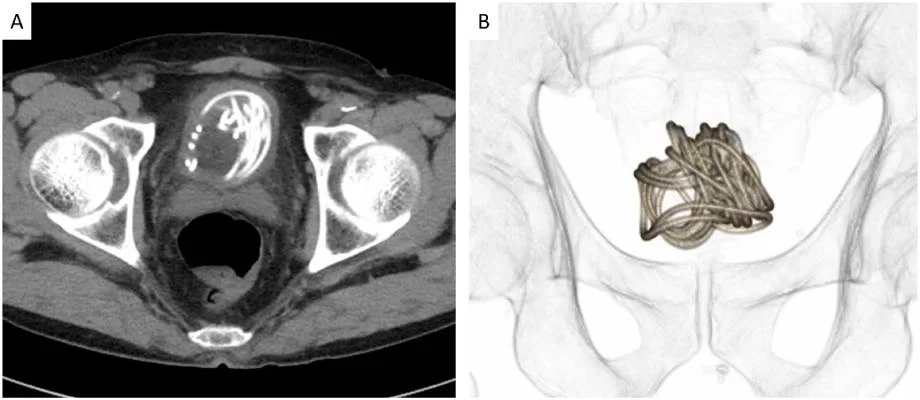

“Primeiro realizamos um ultrassom e identificamos um objeto grande na bexiga do paciente. Depois fizemos um raio-x, que revelou um corpo estranho enrolado em forma de fio. Em seguida, fizemos uma tomografia que nos ajudou a escolher o melhor jeito de tirar a corda e usamos um programa de computador em 3D para nos direcionar. Percebemos que seria impossível puxar a corda pelo pênis”, explicou o médico Toshiki Kijima.